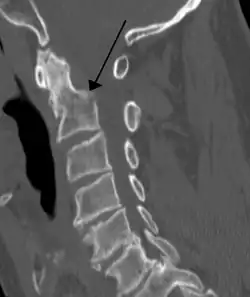

Fractures

Repair of a dens fracture

A fracture of both pedicles of the axis is termed a Hangman's fracture.

Fractures of the dens are classified into three categories according to the Anderson Alonso system:

• Type I fracture - Extends through the tip of the dens. This type is usually stable.

• Type II fracture - Extends through the base of the dens. It is the most commonly encountered fracture for this region of the axis. This type is unstable and has a high rate of non-union.

• Type III fracture - Extends through the vertebral body of the axis. This type can be stable or unstable and may require surgery.[1]